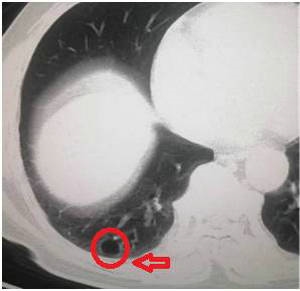

肺大泡,是指由于各种原因导致肺泡腔内压力升高,肺泡壁破裂,互相融合,在肺组织形成的含气囊腔。肺大泡定义为扩张状态下,直径超过1cm的肺内气腔(图1),巨型肺大泡是指至少占据一侧胸腔30%的大泡(图2)。

图一